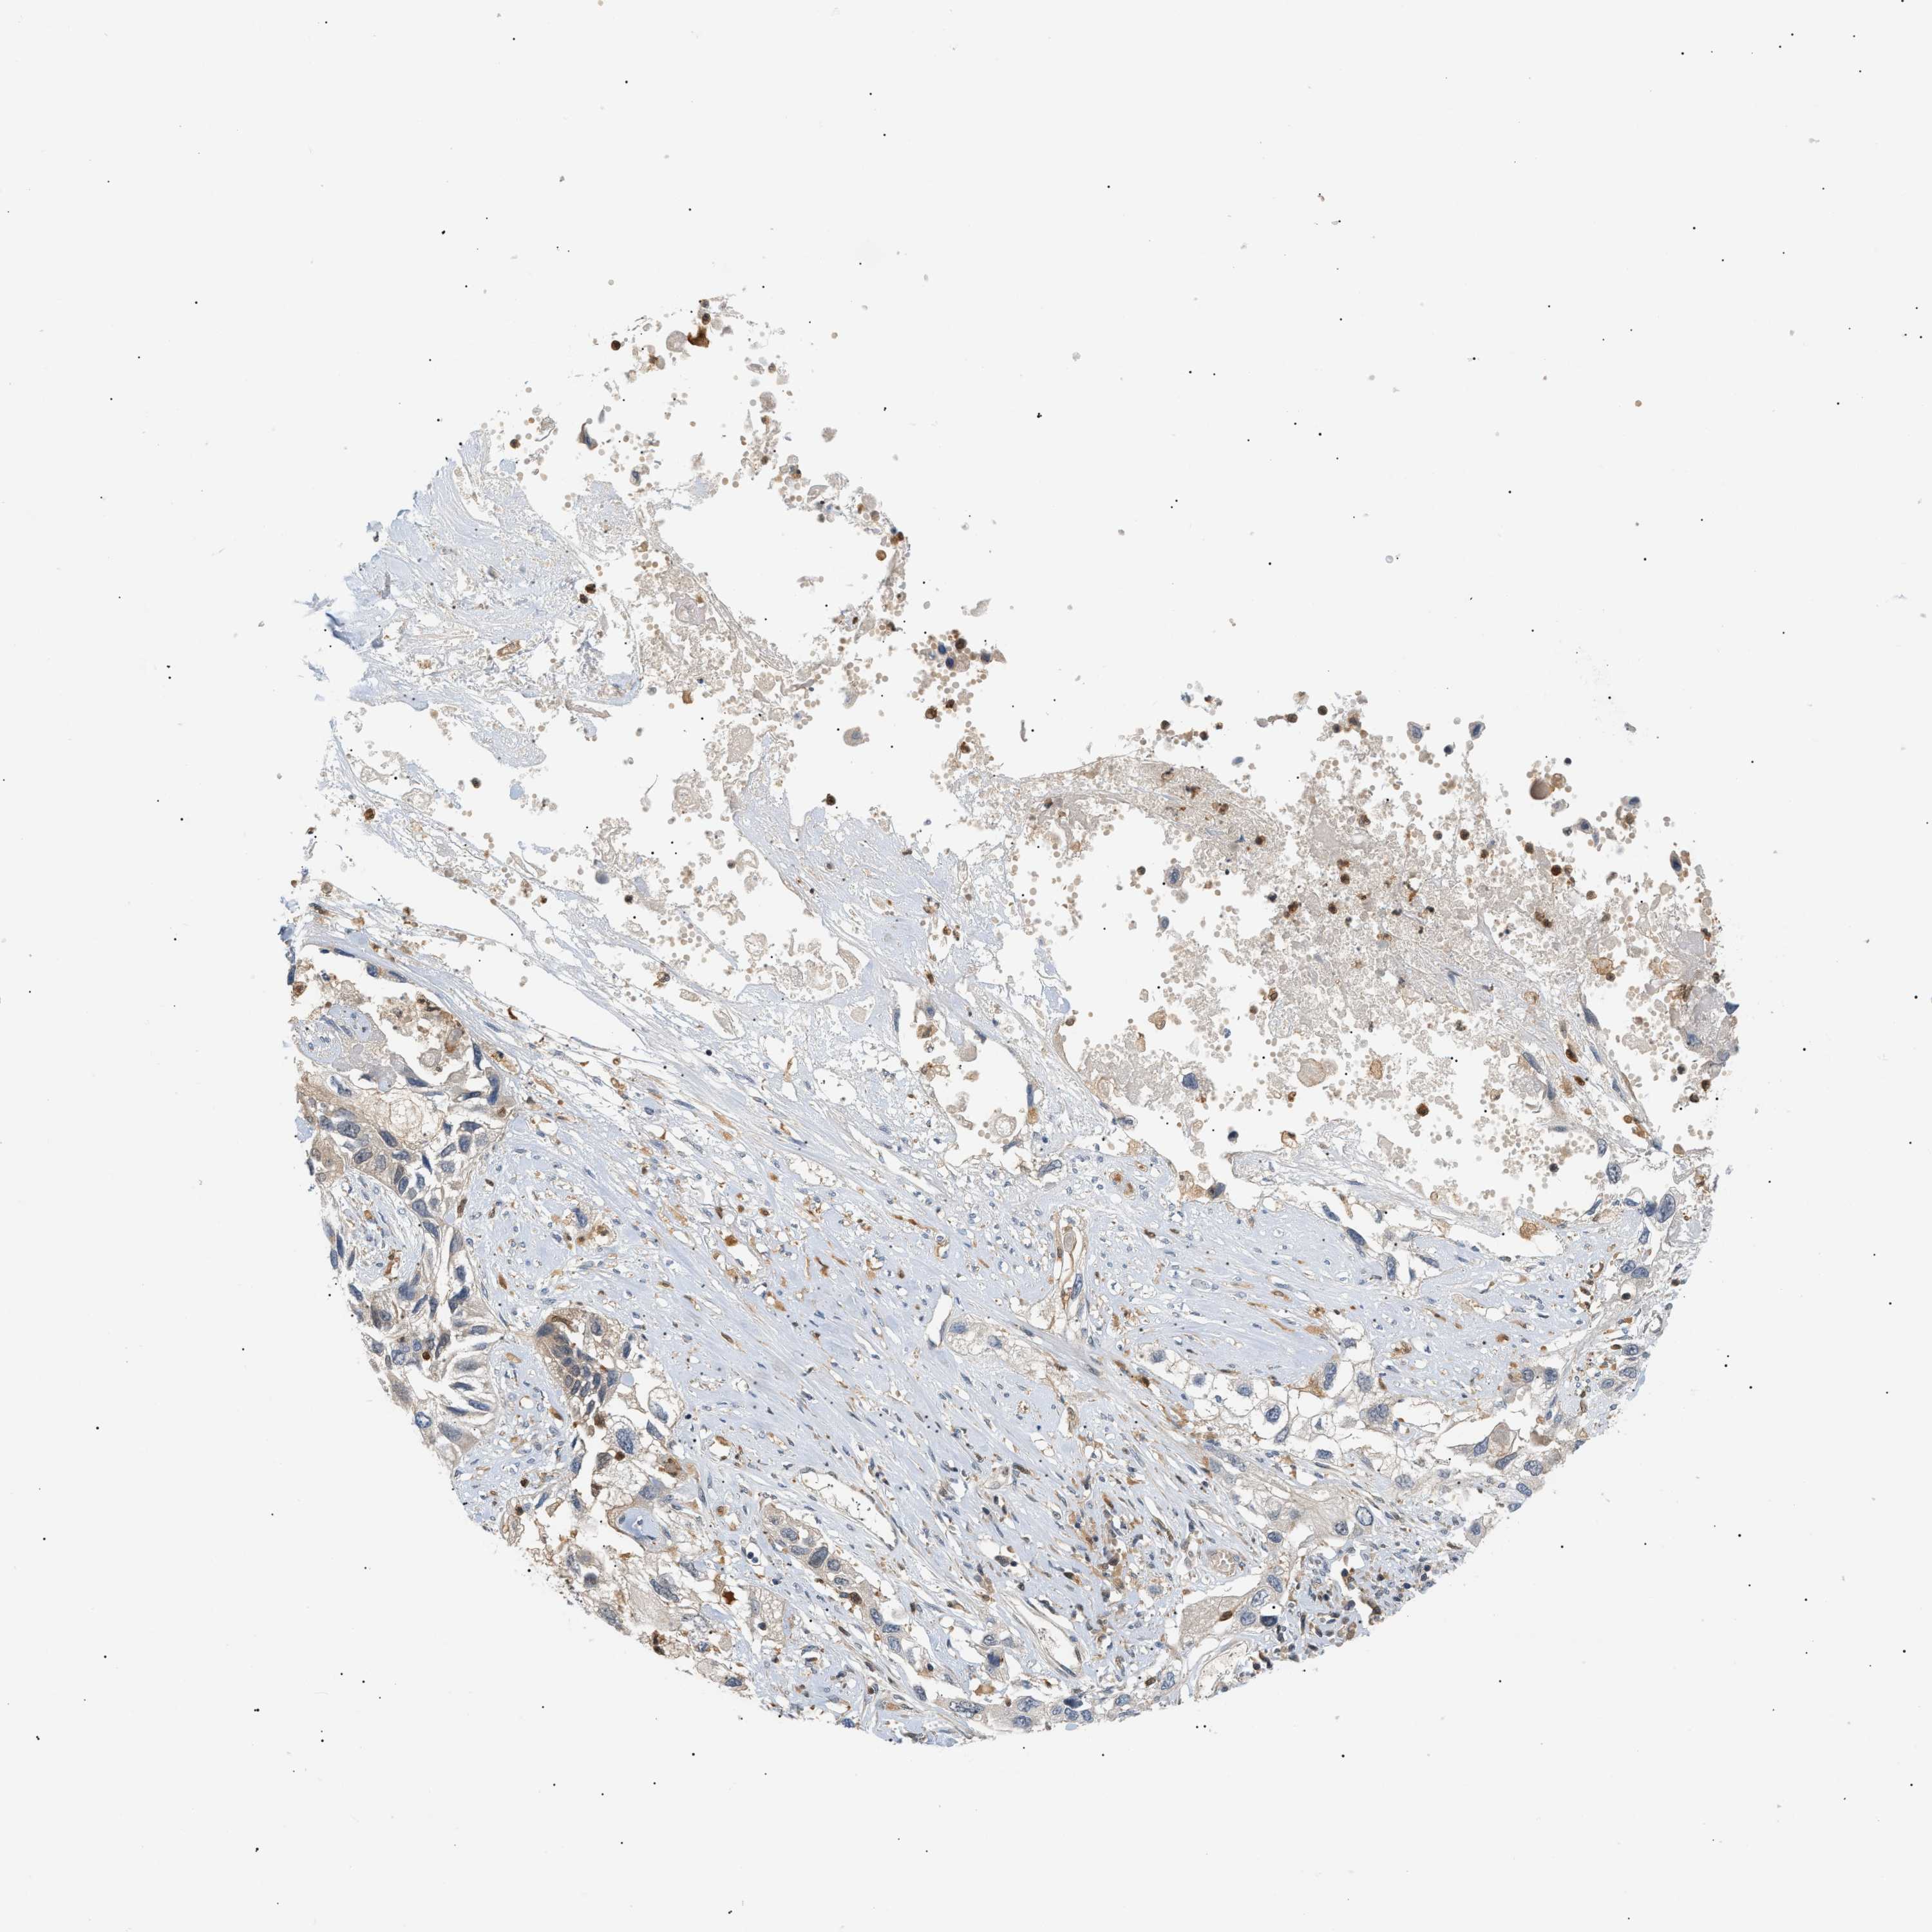

LUNG ADENOCARCINOMA (VALIDATION) - Interactive survival scatter ploti

The Survival Scatter plot shows the clinical status (i.e. dead or alive) for all individuals in the patient cohort, based on the same data that underlies the corresponding Kaplan-Meier plots. Patients that are alive at last time for follow-up are shown in blue and patients who have died during the study are shown in red.

The x-axis shows the expression levels (FPKM) of the investigated gene in the tumor tissue at the time of diagnosis. The y-axis shows the follow-up time after diagnosis (years). Both axes are complimented with kernel density curves demonstrating the data density over the axes. The top density plot shows the expression levels (FPKM) distribution among dead (red) and alive patients (blue). The right density plot shows the data density of the survived years of dead patients with high and low expression levels respectively, stratified using the cutoff indicated by the vertical dashed line through the Survival Scatter plot. This cutoff is automatically defined based on the FPKM cutoff that minimizes the p-score. The cutoff can be changed by dragging the vertical line or by entering a cutoff value in the square labeled "Current cut-off".

Under the Survival Scatter plot the p-score landscape (black curve; left axis) is shown together with dead median separation (red curve; right axis). Dead median separation is the difference in median mRNA expression between patients who have died with high and low expression, respectively. It is calculated as follows: median FPKM expression of dead patients with high expression - median FPKM expression of dead patients with low expression. This is intended to aid the user in visually exploring custom cutoffs and the associated p-scores and dead median separation.

Individual patient data is displayed and can be filtered by clicking on one or more of the category buttons on the top of the page. Categories describing expression level and patient information include: high, low, alive, dead, female, male and tumor stages. The scale of the x-axis can be toggled between linear and log-scale by clicking on the "x log" button. Mouse-over function shows TCGA ID, patient information and mRNA expression (FPKM) for each patient.

& Survival analysisi

Kaplan-Meier plots summarize results from analysis of correlation between mRNA expression level and patient survival. Patients were divided based on level of expression into one of the two groups "low" (under cut off) or "high" (over cut off). X-axis shows time for survival (years) and y-axis shows the probability of survival, where 1.0 corresponds to 100 percent.

PYCARD is not prognostic in Lung Adenocarcinoma (validation)

: 10.75